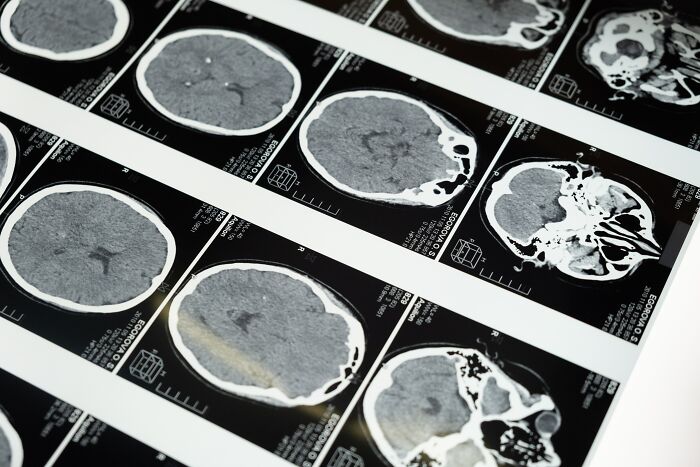

5. “Že využívame len 10 % nášho mozgu.“